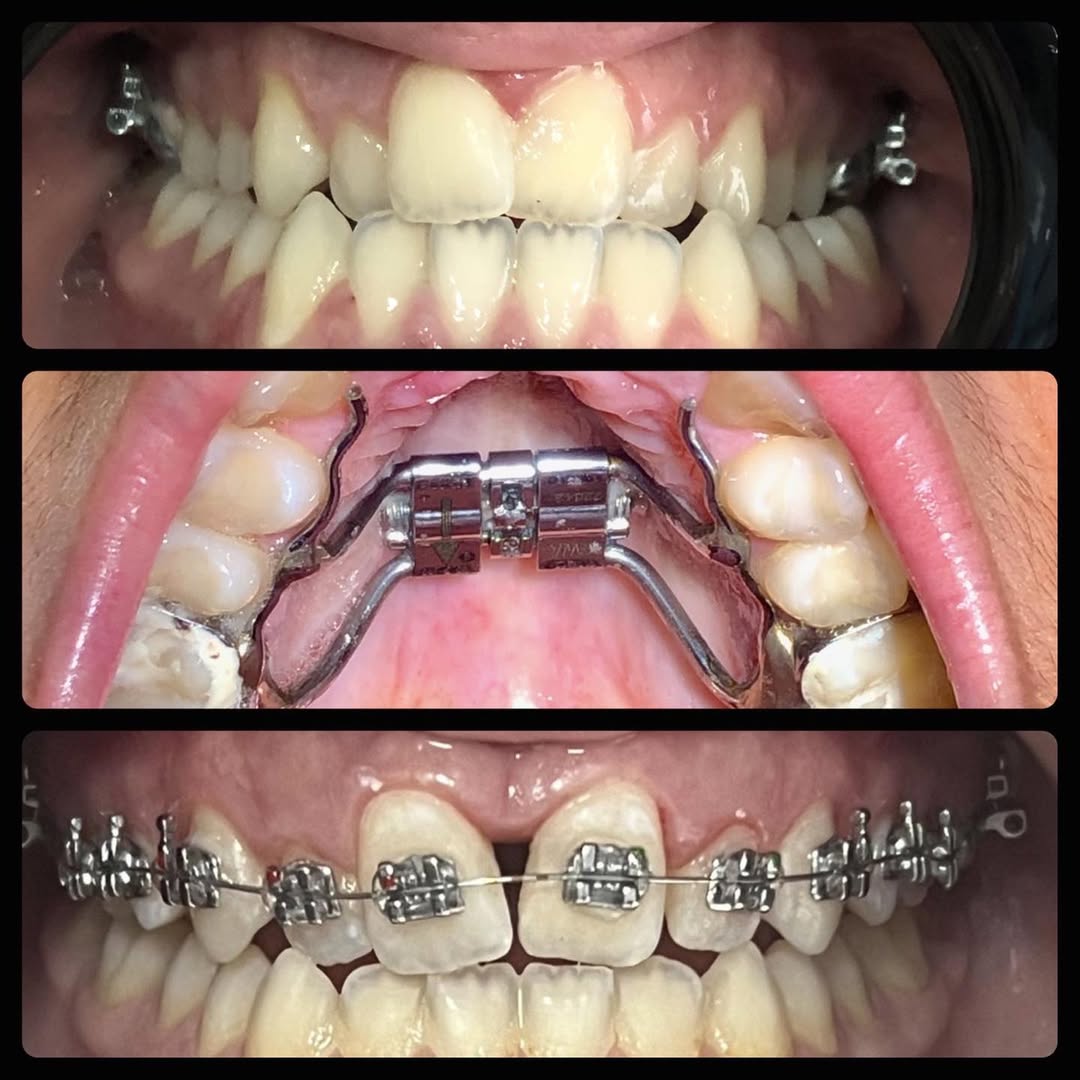

1. Apparecchi Ortodontici Fissi in Metallo

La soluzione classica e più efficace per riallineare i denti in modo stabile e preciso. Indicata per tutte le età e per casi complessi di malocclusione.

3. Apparecchi Autoleganti (Self-Ligating)

Tecnologia avanzata che riduce l’attrito, accorcia i tempi di trattamento e richiede meno controlli periodici.

5. Apparecchi Ortodontici per Bambini

Trattamenti intercettivi e preventivi per guidare la crescita corretta dei denti e delle ossa mascellari, evitando problemi futuri più complessi.